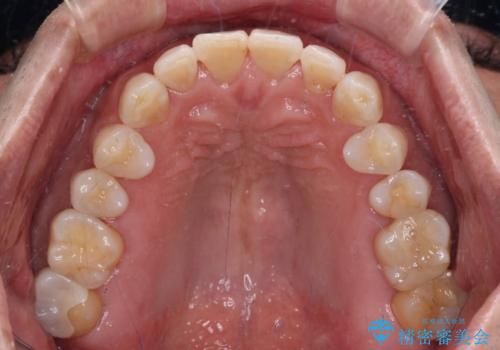

内側にある歯が干渉する 上顎前歯の部分矯正

セラミッククラウンとの干渉はすぐに改善され、歯列も整いましたが、一方で、前歯で食事が噛みにくくなり、1年近い治療期間となりました。